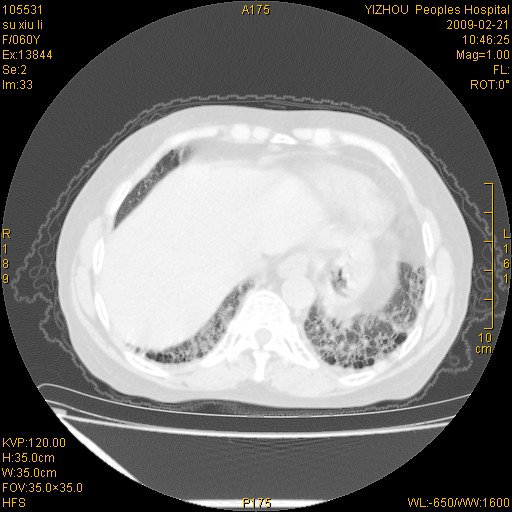

标题: CT18259:两肺间质纤维化? [打印本页]

标题: CT18259:两肺间质纤维化?

女,60岁,反复咳嗽1月。

两肺支扩,以肺为著合并双肺较广范纤维化病变。建议除外结核等病变。

间质性肺炎

符合间质感染,部分纤维化表现

特发性间质纤维化

特发性间质纤维化伴支扩!

间质性肺炎或特发性间质性肺炎